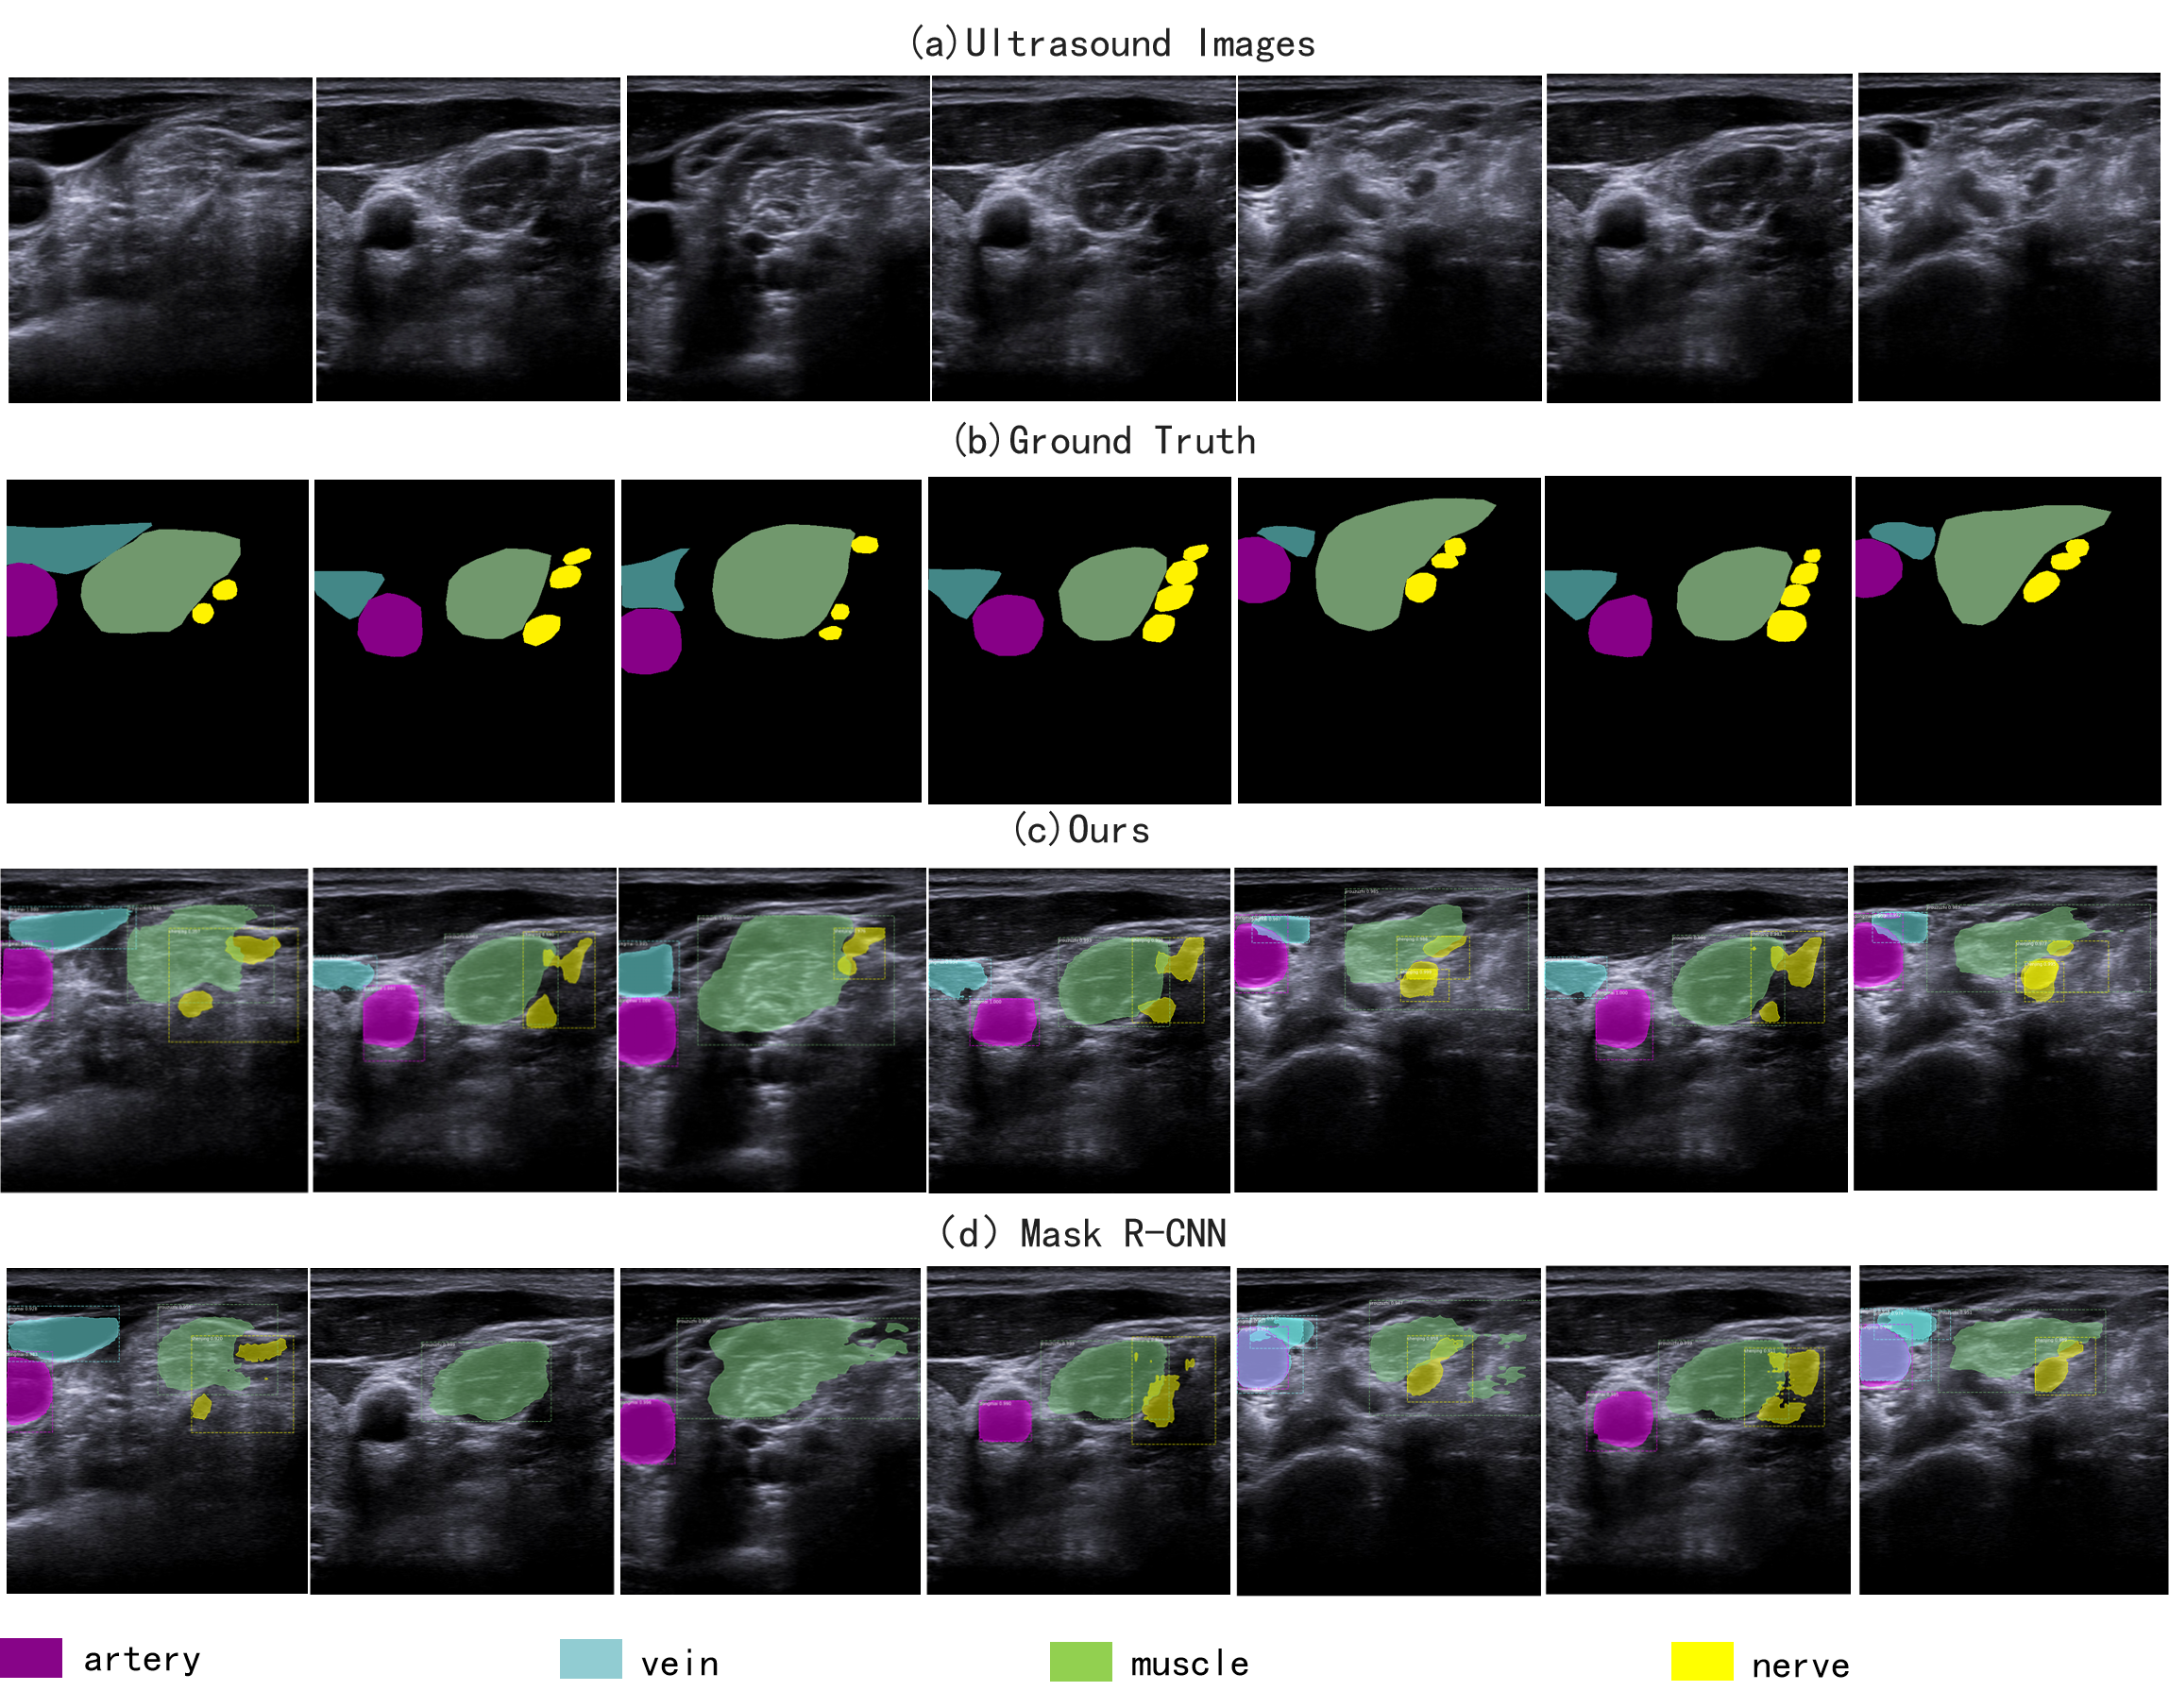

The visualization of segmentation results on the test set of UBPD is shown in the Figure 6, and each row has 7 sampled frames from different videos. The Figure 6 (a) shows the raw ultrasound images blurred by noise interference, in which the nerves are too inconspicuous to identify. The segmentation results of the proposed network are shown in Figure 6 (c), which are very close to ground truth. This indicates that the proposed network can effectively detect and segment different tissues (nerves, arteries, veins, muscles) in ultrasound images, and generate the segmentation results with finer details and smoother edges. However, comparing to the proposed network, the Mask R-CNN fails to effectively segment the nerve and other tissues. As shown in Figure 6 (d), there are instances with wrong segmentation categories and some are even not been identified. These comparison results prove the effectiveness of the proposed network. and the BPMSegNet can achieve a stable and better performance on Brachial Plexus instance segmentation tasks.